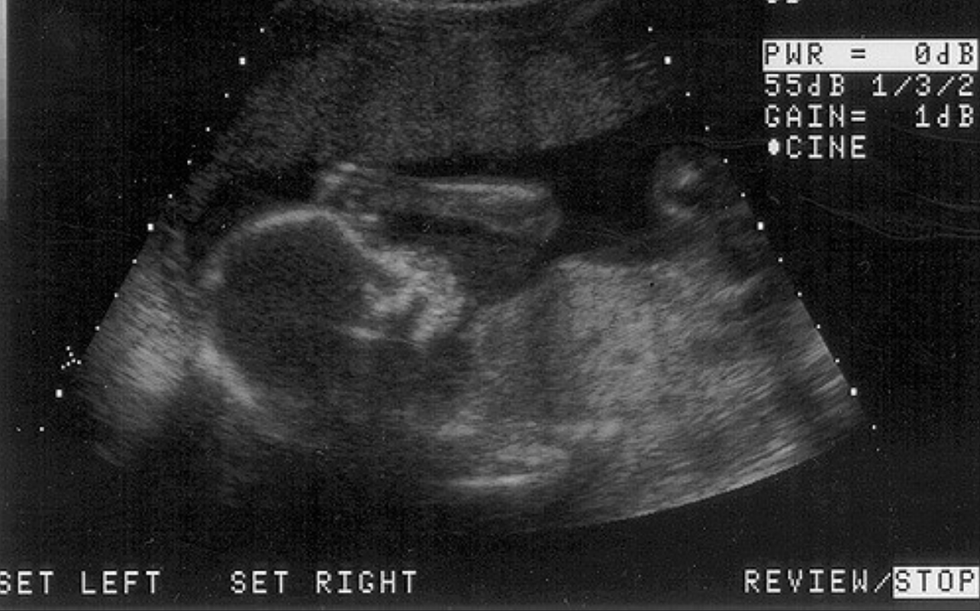

Thankfully, due to science today, we can understand almost every stage of a child’s development. From conception to birth, we can visualize and help mothers understand exactly what is happening inside of them.

Here a rough calendar of a baby’s development.

Weeks 1-4: This period is before most women are aware they are pregnant. The baby is just a group of cells right now, smaller than the head of a pin. During this stage, the brain, spinal cord, heart, and gastrointestinal tract develops. This leads to the development of the circulatory system and the fetal skeleton, which initiates the organ and muscle development.

Weeks 5-13: This time period is when most abortions occur. Women become aware they are pregnant and decide to receive an abortion.

During the first couple weeks, the baby looks kind of like a tadpole. We can see the head, heart, and spinal cord developing nicely. There is a steady heartbeat we can hear at this stage. The fetal skeleton is forming.

At week 7, every vital organ the baby needs to survive has begun to develop. At week 9, babies will begin to suck their thumbs. Weeks 10-12, the baby continues to grow and most organs have started developing.

At week 13, the baby has its own unique fingerprints.

Weeks 13-21: About 7% of abortions occur during this time. At this point, the ears and eyes are in their final positions so the baby’s appearance is identifiable. The urinary and circulatory functions are beginning to function. At week 14, the baby’s facial muscles can move. This means the baby can express emotions through frowning, squinting, and grimacing. At week 16, the baby’s heart is pumping 25 quarts of blood a day.

Most critical development has been completed, the likelihood of a miscarriage decreases. The baby only needs to continue to grow and develop to be a good, healthy baby.

Weeks 21-40: Abortions during this stage of pregnancy is almost none existent, about 2% of all abortions. This is the halfway point of the pregnancy. The baby is now measured from the head to the feet. By week 30, the babies’ lungs and brain are well developed. By week 38, all organs and muscles are functioning. During the last couple weeks, premature labor is common. Mothers can expect a healthy developed baby.